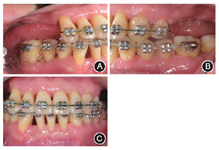

术后(3)正畸:2012年7月至2013年11月,上下颌牙齿分别开始正畸加力(图6,图7),期间每3个月进行一次牙周维护。

像(4)种植:2013年11月,牙周复查显示牙周状况稳定,开始行

同期GBR植骨(图8)。2014年2月,取模制作临时冠,作为正畸支抗继续正畸治疗。2014年11月,拆除固定矫治器,制作保持器,牙周复查情况稳定(图9,图10)。

末次复查结果显示患者口腔卫生状况良好,牙周状况稳定(图11,图12,图13)。解决了前牙间隙问题,恢复了后牙的咀嚼功能,患者对疗效满意。